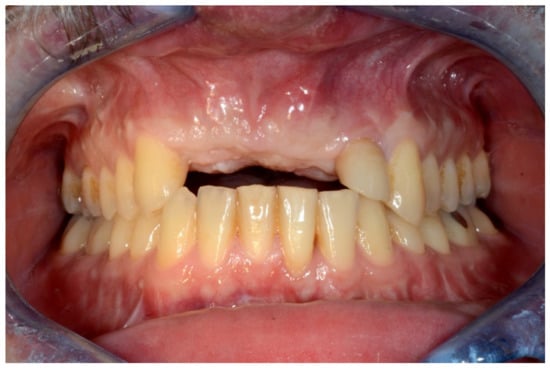

Figure 1.

Frontal view showing the edentulous defect.